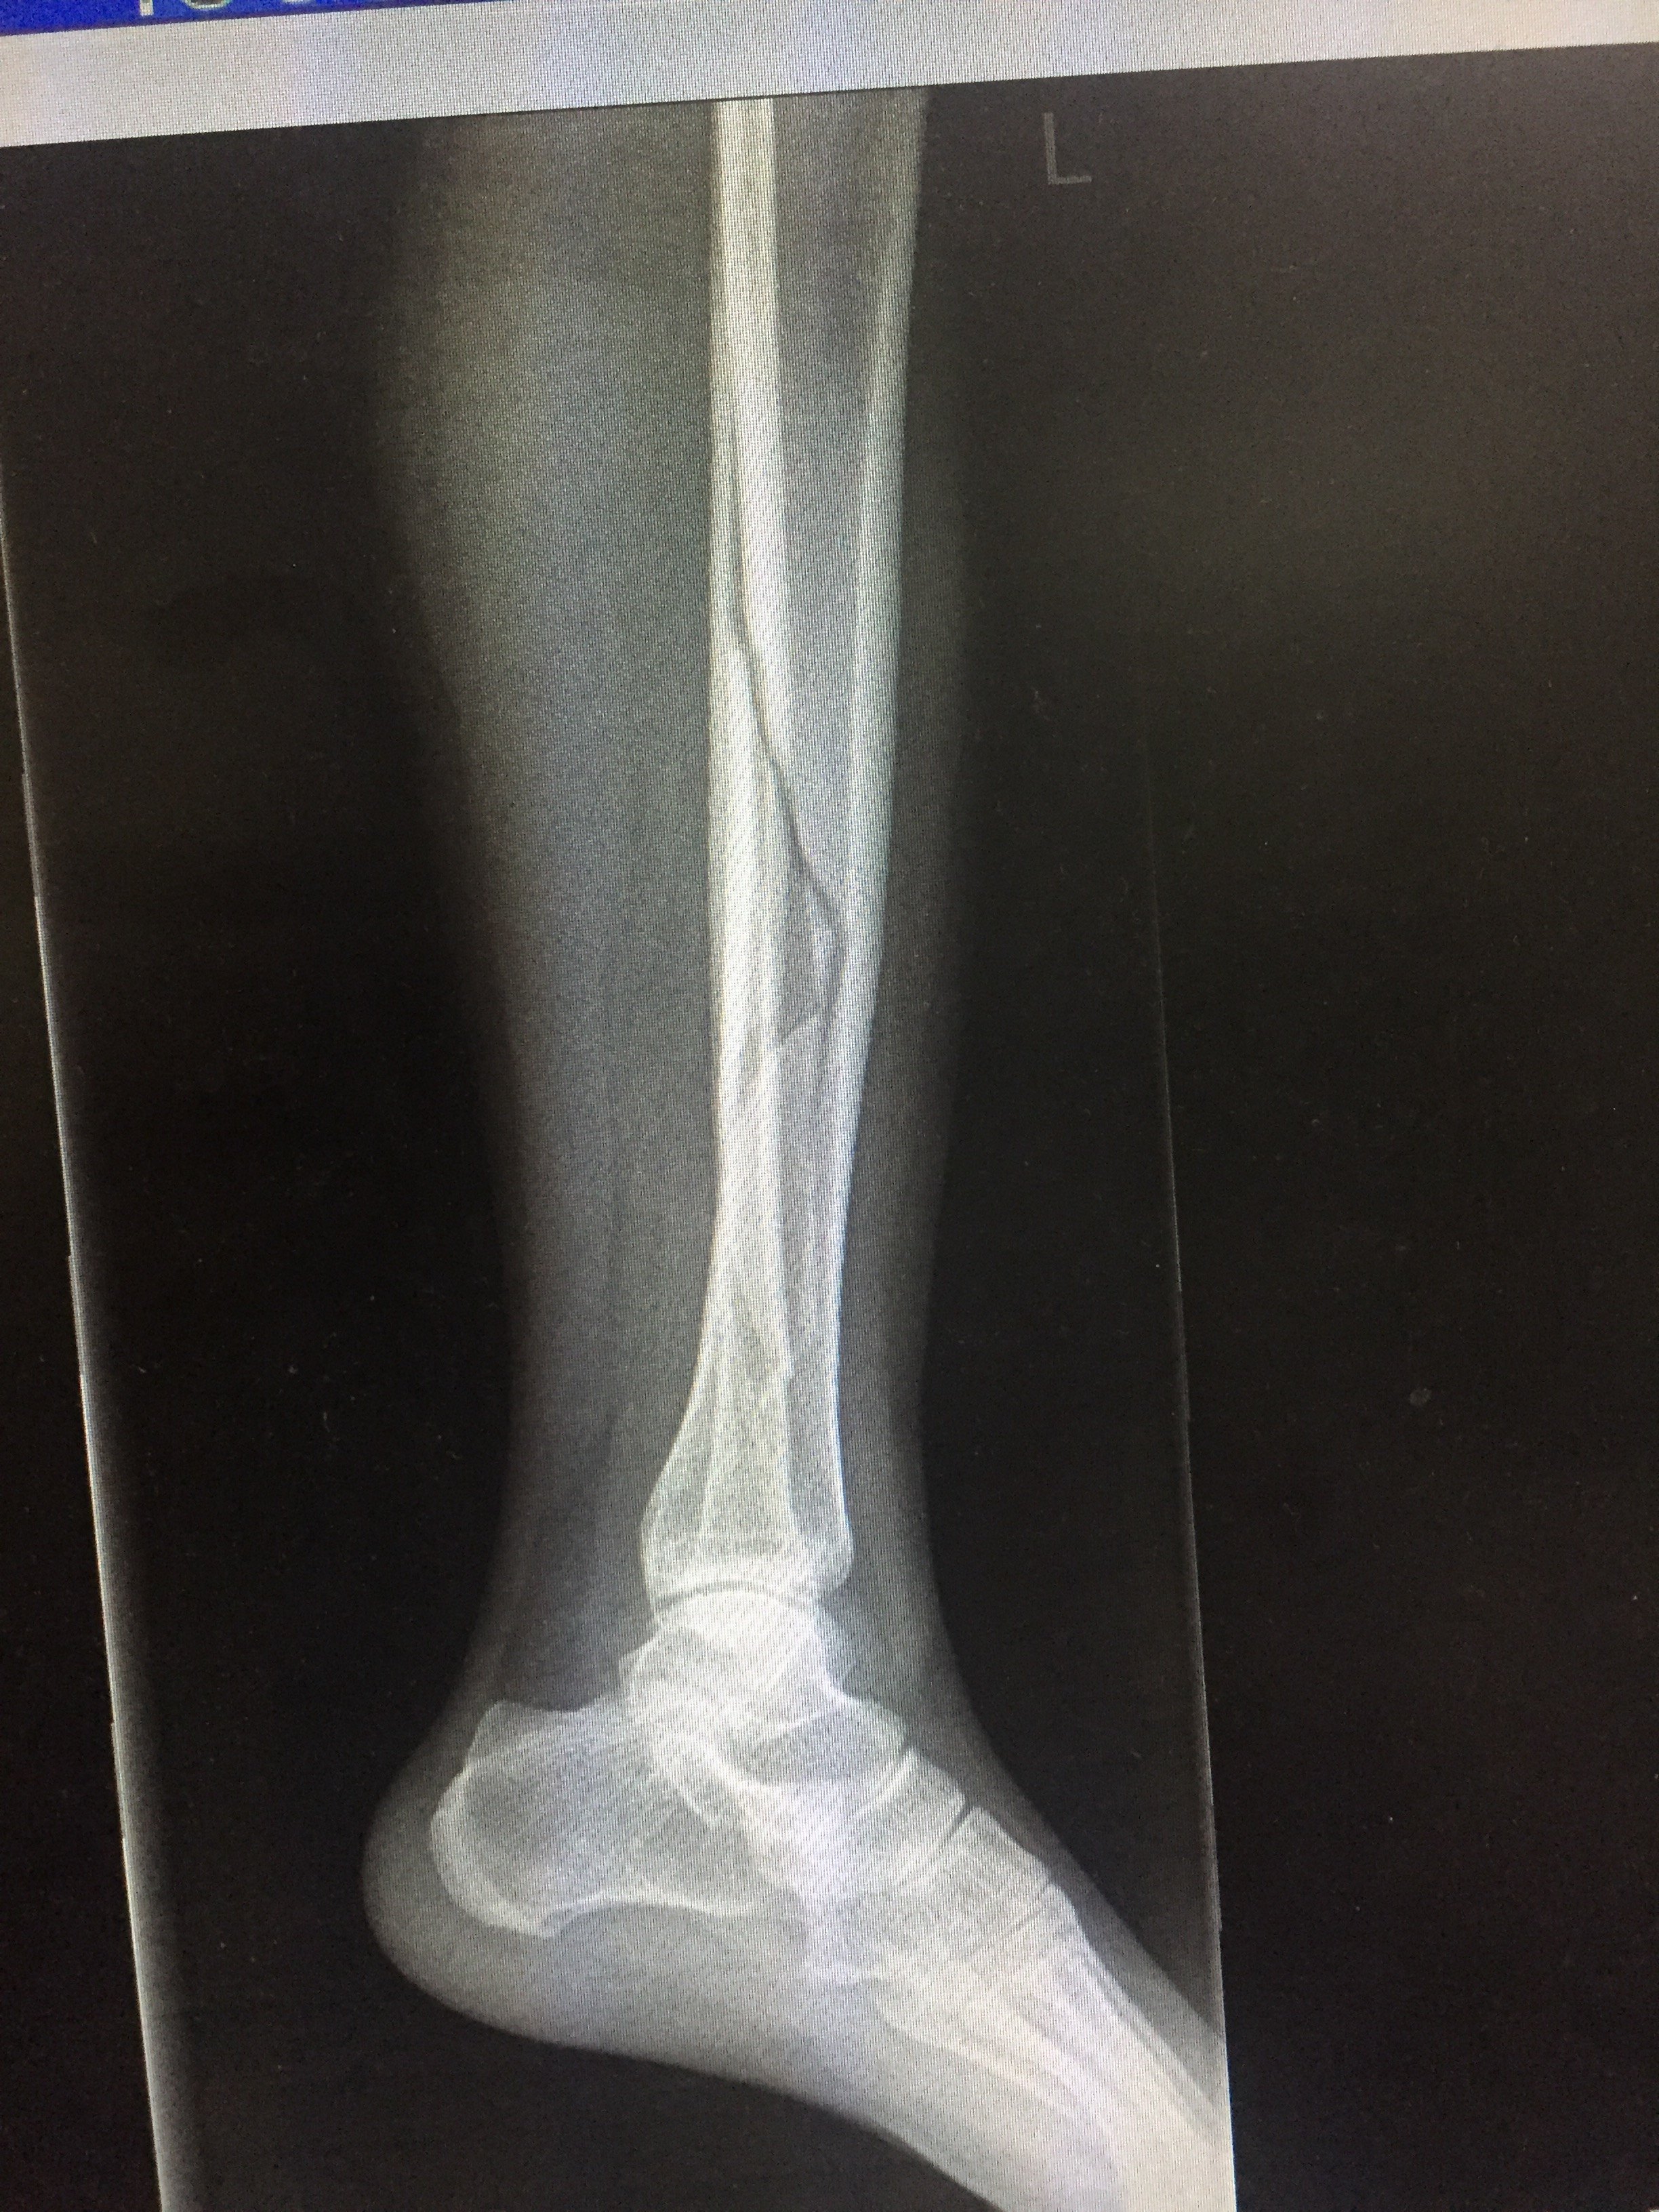

腓骨単独骨折 遠位1/3は足関節が不安定になるので転位がある場合は手術を行います。 遠位1/3より頭側(中枢側)は保存的治療が選択されます。 保存的治療の外固定は23週間とし足関節の可動域訓練を行うようにします。6日に左腓骨(ひこつ)骨折に対する固定術を受け、無事終了した。 今後は、3カ月以内での実戦復帰を目 掲載媒体:なんJスタジアム 西武外崎修汰が左足腓骨骨折で手術 復帰早くて7月中旬、五輪出場厳しく 転載元 httpsDec 06, 17 · 交通事故の被害に遭い、脛骨骨折や腓骨骨折の怪我を。 その後、もしも後遺症が残ってしまったとしたら。 これからも長く続く治療やリハビリの生活では、 脛骨骨折・腓骨骨折から回復するために支払う治療費 怪我をしたことや後遺症が残ったことによる精神的苦痛に対する慰謝料

11 年 7 月 24 日 アラフォーにして人生初の 骨折 & 手術 骨折 から 完治 までの 骨折記録 骨折 して 日たったけど、この先どうなるの? など 実際私が知りたかった 生の声 を 骨折 してしまった皆様に ちょっとでもわかりやすくお届けできたらいいなぁ・・・脛骨および腓骨のストレス骨折 stress fractures of the tibia and fibula 2 Posterior cruciate ligament injury 3 小児における脛骨および腓骨骨幹部骨折 tibial and fibular shaft fractures in children 4 小児における足関節骨折 5 腓骨骨折の手術やリハビリとは?腓骨はとても細い骨ですが、足関節も構成するためとても重要な骨です。 腓骨骨折の手術やリハビリとは? みなさんの周りにも足首を骨折した方がいらっしゃると思います。 足関節の骨折は脛骨や腓骨のくるぶし部分の骨折です。

胫腓骨骨折手术后图片 第1页 一起扣扣网

骨折から1年と1か月、とうとうプレートとボルトを抜く抜釘手術を受けてきました。 骨折の経緯は下記 アイスクライミングで右足果部 腓骨・脛骨骨折 復帰までの記録 ①受傷から手術~退院まで ムカデのおにいさんのブログ アイスクライミングで右足果部腓骨・脛骨骨折 復帰までの記録 ②脛骨骨折・腓骨骨折の後遺症|回復へのリハビリや治療費・慰謝料などの示談金は!? 交通事故の被害に遭い、脛骨骨折や腓骨骨折の怪我を。 その後、もしも後遺症が残ってしまったとしたら。 これか 続きを読むDec 22, 15 · 下腿骨骨折の場合、成人であれば軽症のものを除き手術が行われます。ただしご高齢の方や心臓、肺、その他の臓器に持病がある方などで手術を行うリスクが大きい場合、また骨折自体が小さなものであったり、小児の骨折の場合などは、自然に骨がつくのを待つこともあります。